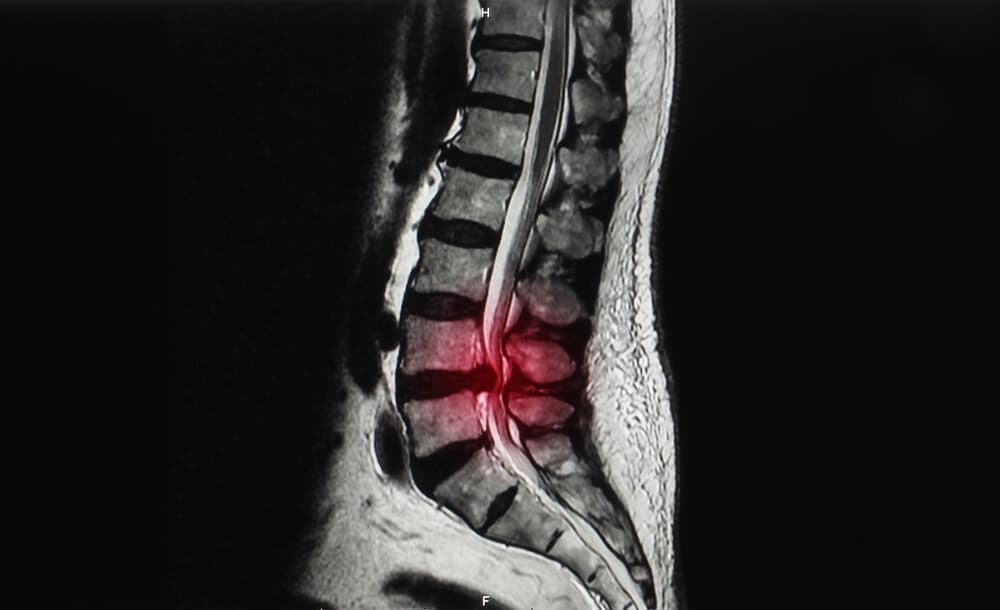

背骨(脊柱)にある椎骨という骨にズレが生じている状態のことを腰椎すべり症と呼ばれています。

背骨(脊柱)は、椎骨がいくつも連結して形成されています。

すべりが生じることにより腰椎が安定せず、神経が通っている脊柱管が狭窄して神経に圧力を与えます。